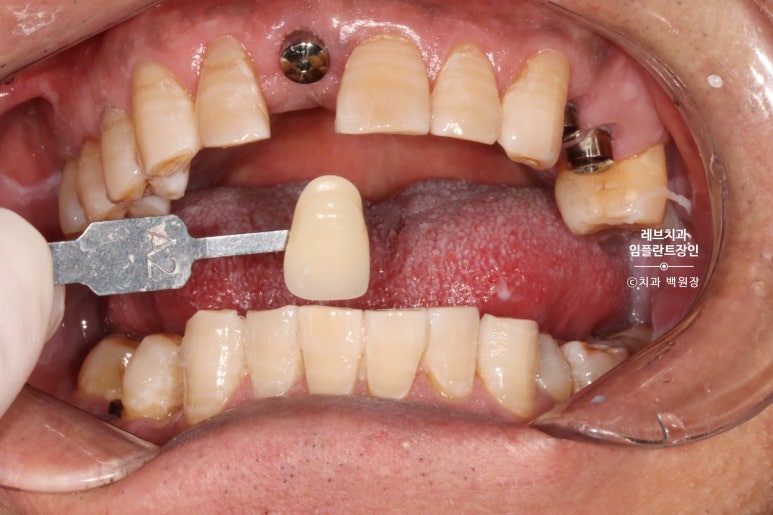

역시나 치아 색을 정하기 위해 shade guide를 이용하여 치아색 측정을 열심히 해봅니다.

어른들의 치아를 자세히 보시면, 생각보다 색구현이 어렵게 생겼음을 확인하실 수 있을거에요 ^^;;;

그리하여 유사하게 만들어본 앞니입니다.

왼쪽 위 작은 앞니와 송곳니를 합쳐서 2개짜리 보철물을 만들었어요!